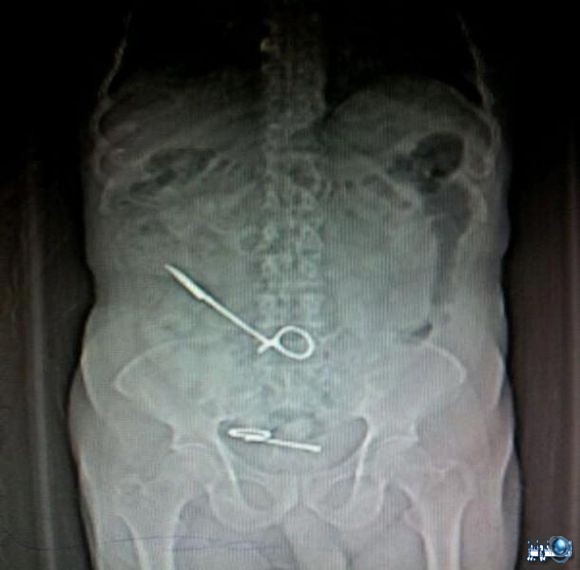

مقص في البطن

بتاريخ 18 يناير 2015، كشف المحضر رقم 336 إداري لسنة 2015 الذي حررته أسرة المريض وحيد كمال السيد “50 عاما”، في قسم شرطة العطارين بالإسكندرية، عن أن المريض دخل لإجراء عملية جراحية لاستئصال جزء من الأمعاء مطلع شهر ديسمبر الماضي، إلا أنه وعقب خروجه تعرض لمضاعفات صحية خطيرة.

وأضاف المحضر أن المريض المذكور عقب خروجه من المستشفى شعر بتحسن كبير في حالته الصحية حتى عاودته الآلام الشديدة، وقام بتوقيع الكشف الطبي وإجراء الأشعة إلا أن طبيب الأشعة المعالج اكتشف وجود مقص داخل بطن المريض بطول 40 سم، فتوجهت أسرته لإجراء أشعة بأحد المراكز الخاصة، وثبت صحة الأمر بعد أن أنكر الأطباء صحة الواقعة، مشيرين إلى أن ما حدث هو التهابات بالقولون.

واتهم المحضر 3 من الأطباء بالتسبب في هذا الإهمال، بعد أن حاولوا نفي الواقعة، وأكدوا ضرورة دخول المريض العناية المركزة مرة أخرى، وكتبوا له تصريح دخول مرة أخرى لإجراء جراحة جديدة لاستخراج المقص، بعدما أشاروا لأسرة المريض أن ما حدث أمر طبيعي ولا مخاوف على حالة المريض، فدخل المستشفى الثلاثاء الماضي وأجريت له الجراحة إلا أنه ومنذ هذا التاريخ وهو يعاني بسبب سوء المعاملة والإهمال.